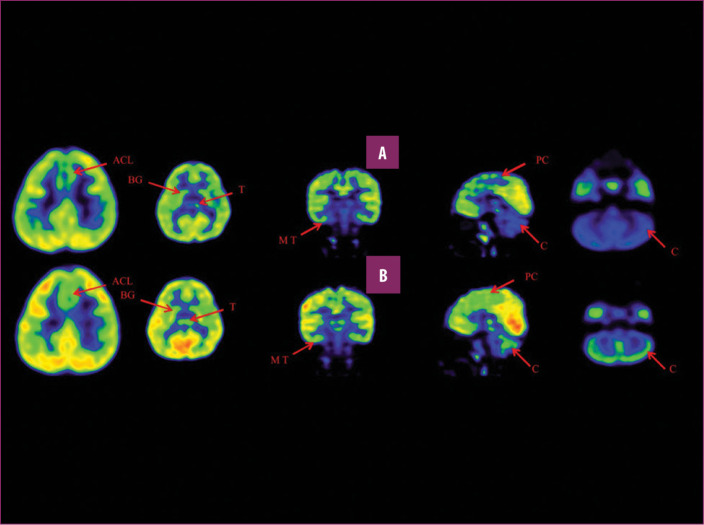

前扣帶回 (ACL)、頂葉皮層 (PC)、內側顳葉皮層 (MT)、基底神經節 (BG)、丘腦 (T) 和小腦 (C)。B 行)第一次移植后6個月后PETCT腦部掃描的干預后圖像顯示標記區域有所改善。藍色代表代謝減退區域。綠色代表正常的新陳代謝區域。圖A和B的比較顯示藍色區域顯著減少,綠色區域增加,這表明大腦的新陳代謝得到改善。

與之前的情況相比,他在矢狀面和額狀面上的體重變化有所改善;頭部、軀干和骨盆的排列也得到改善,雙側腿筋和小腿肌肉的緊繃感也有所減輕。患者開始執行雙手任務。在認知方面,由于他定期上學,他的注意力持續時間和久坐耐力也得到了改善。GMFM評分從60.67提高到67.75;GMFCS等級由Level3提升至Level2;和FIM評分從97分提高到99分。在比較第一次細胞治療之前和之后七個月期間進行的腦部PETCT掃描結果時,前扣帶葉、頂葉皮層、內側顳葉皮層、丘腦、基底神經節和小腦(表格1)。